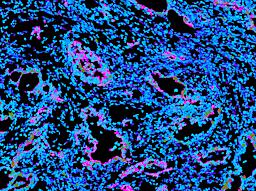

Pancreatic ductal adenocarcinoma is a lethal disease with limited treatment options and poor survival. We studied 83 spatial samples from 31 patients (11 treatment-naïve and 20 treated) using single-cell/nucleus RNA sequencing, bulk-proteogenomics, spatial transcriptomics and cellular imaging. Subpopulations of tumor cells exhibited signatures of proliferation, KRAS signaling, cell stress and epithelial-to-mesenchymal transition. Mapping mutations and copy number events distinguished tumor populations from normal and transitional cells, including acinar-to-ductal metaplasia and pancreatic intraepithelial neoplasia. Pathology-assisted deconvolution of spatial transcriptomic data identified tumor and transitional subpopulations with distinct histological features. We showed coordinated expression of TIGIT in exhausted and regulatory T cells and Nectin in tumor cells. Chemo-resistant samples contain a threefold enrichment of inflammatory cancer-associated fibroblasts that upregulate metallothioneins. Our study reveals a deeper understanding of the intricate substructure of pancreatic ductal adenocarcinoma tumors that could help improve therapy for patients with this disease.